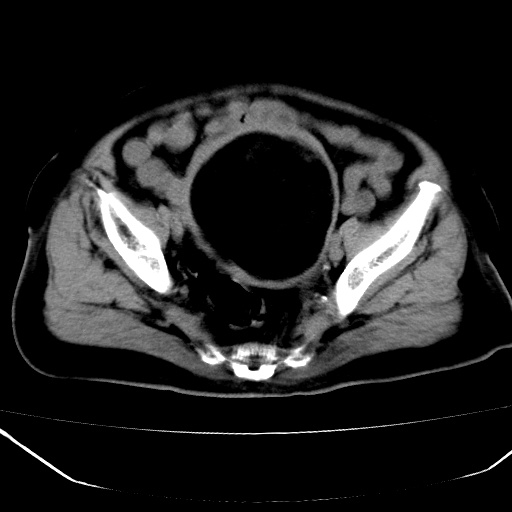

患者,女,74岁,无不适,b超示盆腔包块。

子宫前上方巨大脂性肿物,肿物边缘为较厚软组织密度影,其内缘欠光整,脂性密度中央见结节状软组织密度影“漂浮”,肿物与子宫前壁关系密切,考虑1脂肪瘤2皮样囊肿3肌瘤脂样变

ct值-90hu